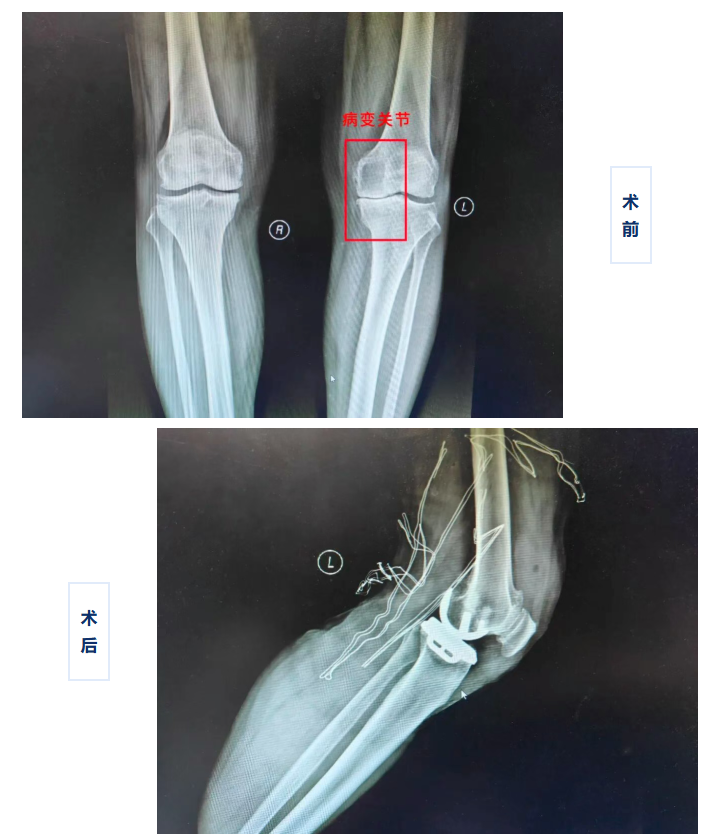

经过详细的影像学检查,刘阿姨的膝关节疼痛主要源于内侧间室的严重磨损,而外侧间室及前后交叉韧带均功能完好。针对这一情况,手术团队没有选择传统的全膝置换,而是为其量身定制了更精准的微创单髁置换术。

骨外科医师吴世昌介绍:“膝关节单髁置换术是只置换膝关节中受损最严重的‘一个间室’,如同给一颗坏掉的牙齿做牙冠,而不是把所有的牙都换掉。”与传统全膝关节置换相比,单髁置换术具有创伤更小、出血更少、恢复更快、费用更低的优势,能最大程度地保留患者膝关节的正常结构和功能,术后膝关节的感觉和活动度也更接近正常关节。

手术中,骨外科手术团队操作精准,仅通过一个微小切口便完成了病变间室的置换。术后第二天,刘阿姨在医护人员指导下行走,她惊喜的说:“我的膝盖不疼了,腿也直了,感觉就像换了个新关节一样!”